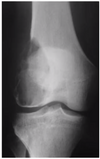

33

# Princípios básicos de tumores ósseos - Com base na imagem, classifique de acordo com Enneking:

- **B2 → ativo** (*afila a cortical*)